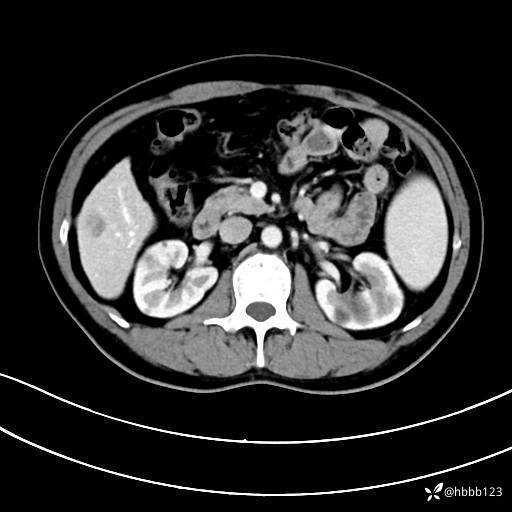

门诊完善上腹部CT平扫+增强。

动脉期: